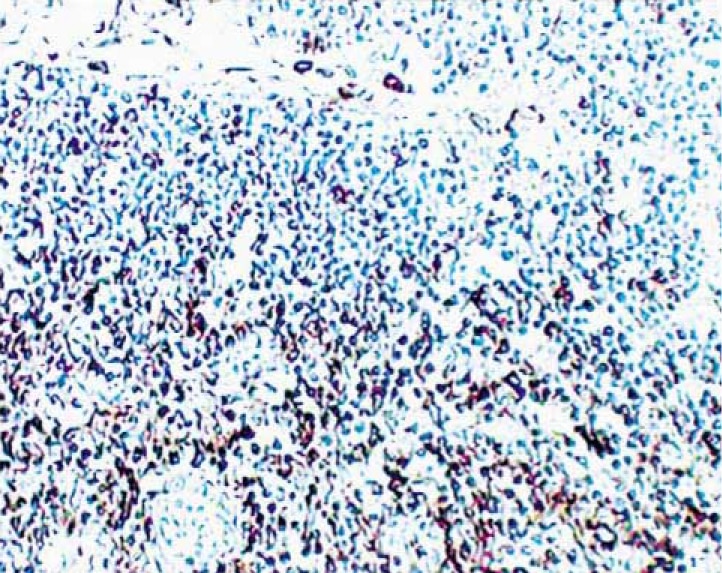

Immunohistochemical staining of CD44+ cells. Paraffin sections of normal human thymus were reacted with Purified Mouse Anti-Human CD44 G44-26 (Cat. No. 550392) antibody. Thymocytes can be identified by the brown labeling of their cell surface membranes. Amplification 20X.

Immunohistochemistry: The G44-26 antibody is recommended to test for immunohistochemical staining of acetone-fixed frozen sections and formalin-fixed paraffin sections with citrate pre-treatment. Tissues tested were human spleen, thymus and tonsil. The antibody stains thymocytes, leukocytes, erythrocytes and weakly on platelets. The isotype control recommended for use with this antibody is purified mouse IgG2b (Cat. No. 557351). For optimal indirect immunohistochemical staining, the G44-26 antibody should be titrated (1:10 to 1:50 dilution) and visualized via a three-step staining procedure in combination with polyclonal, biotin conjugated anti-mouse Igs (multiple adsorbed) (Cat. No. 550337) as the secondary antibody and Streptavidin-HRP (Cat. No. 550946) together with the DAB detection system (Cat. No. 550880). A detailed protocol of the immunohistochemical procedure is available on our website at http://www.bdbiosciences.com/us/s/resources.